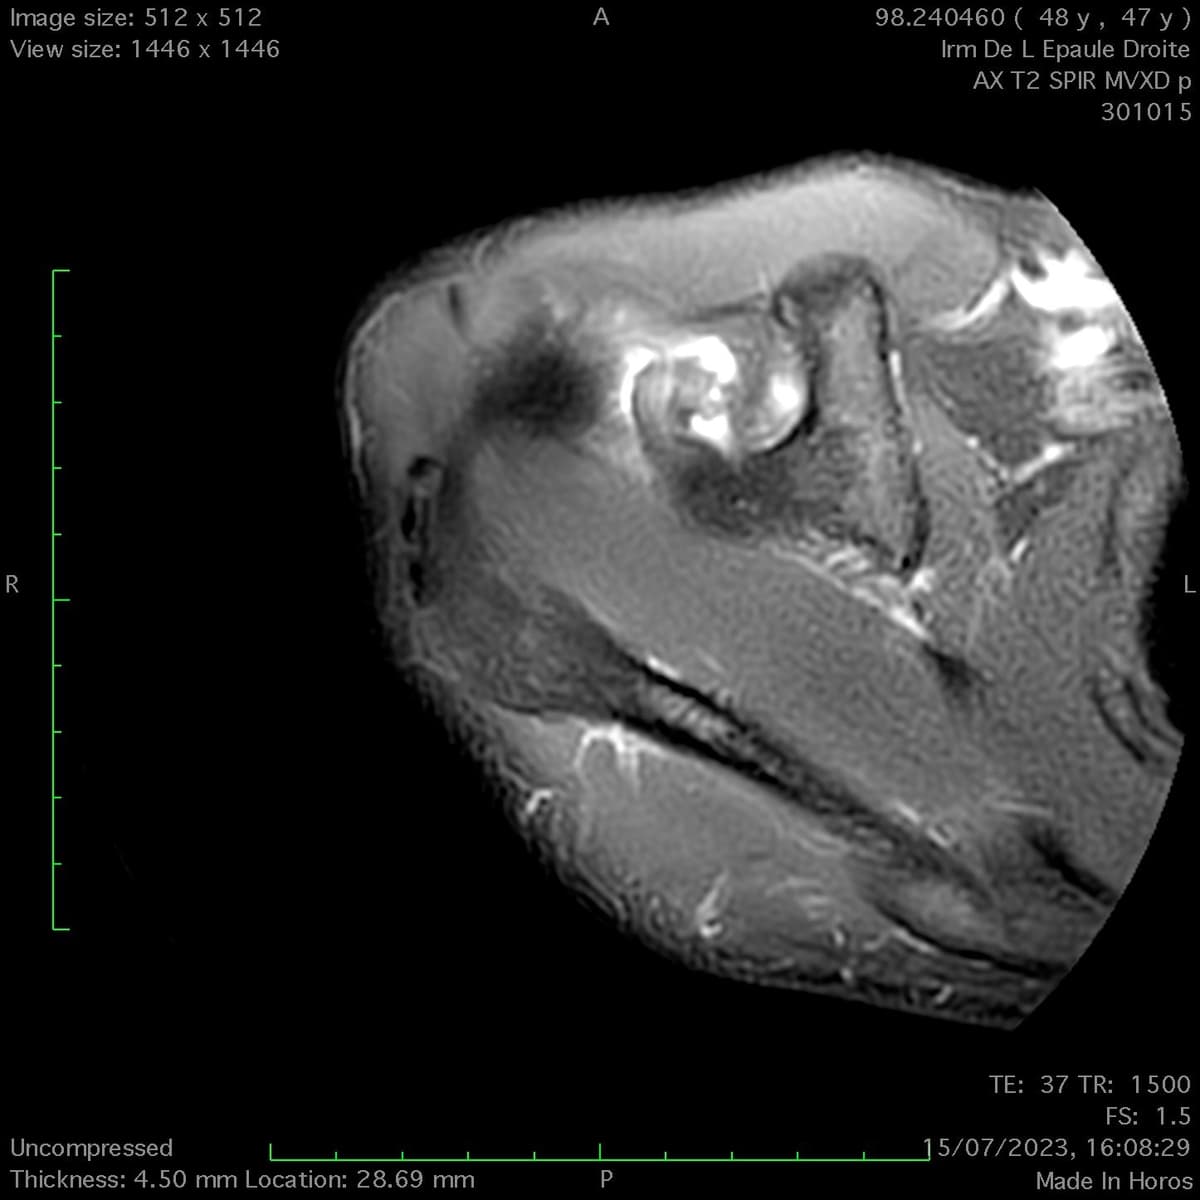

Rupture proximale du tendon du biceps

Rupture proximale du tendon du biceps de l'épaule

Lésion traumatique brutale de la portion intra articulaire du biceps de l'épaule droite